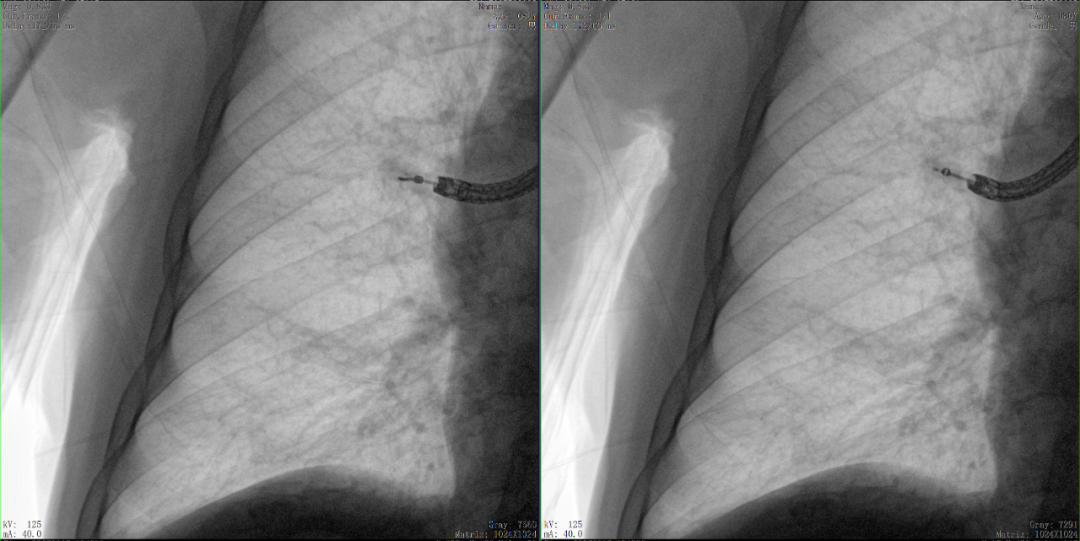

病例1:右側股骨遠端骨骺骨病(13歲)

二維影像看不到病灶點

三維切面影像可以看出病灶點